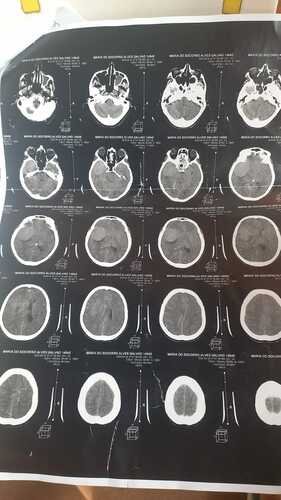

Recentemente, Maria do Socorro recebeu o diagnóstico devastador de um tumor na cabeça. Esta notícia abalou não só ela, mas todos nós que a amamos e admiramos. No entanto, Maria do Socorro é uma lutadora e está determinada a vencer esse tumor.

Para isso, ela precisa passar por uma cirurgia crucial. Esta cirurgia é sua melhor chance de vencer o tumor e recuperar sua saúde. No entanto, os custos associados a este procedimento são significativos, e é por isso que estamos lançando esta vaquinha online.